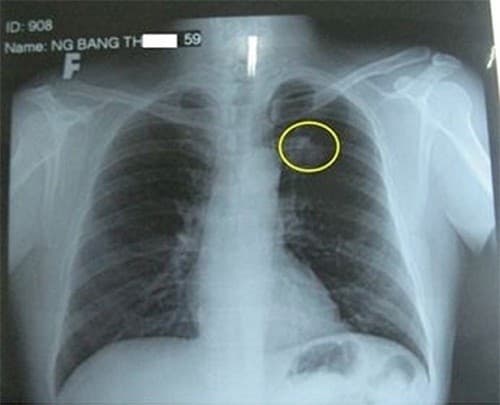

Người bệnh chỉ có thể thấy được hình ảnh ung thư phổi khi tiến hành chụp X-quang ngực. Ngoài ra có thể kết hợp chụp CT/ MRI để chẩn đoán bệnh tiến triển và di căn sang các vị trí khác hay chưa.

Hình ảnh ung thư phổi này giúp nhận biết các giai đoạn bệnh cụ thể.

Từ đó bác sĩ sẽ chỉ định phẫu thuật hoặc hóa trị để loại bỏ tế bào ung thư phổi.